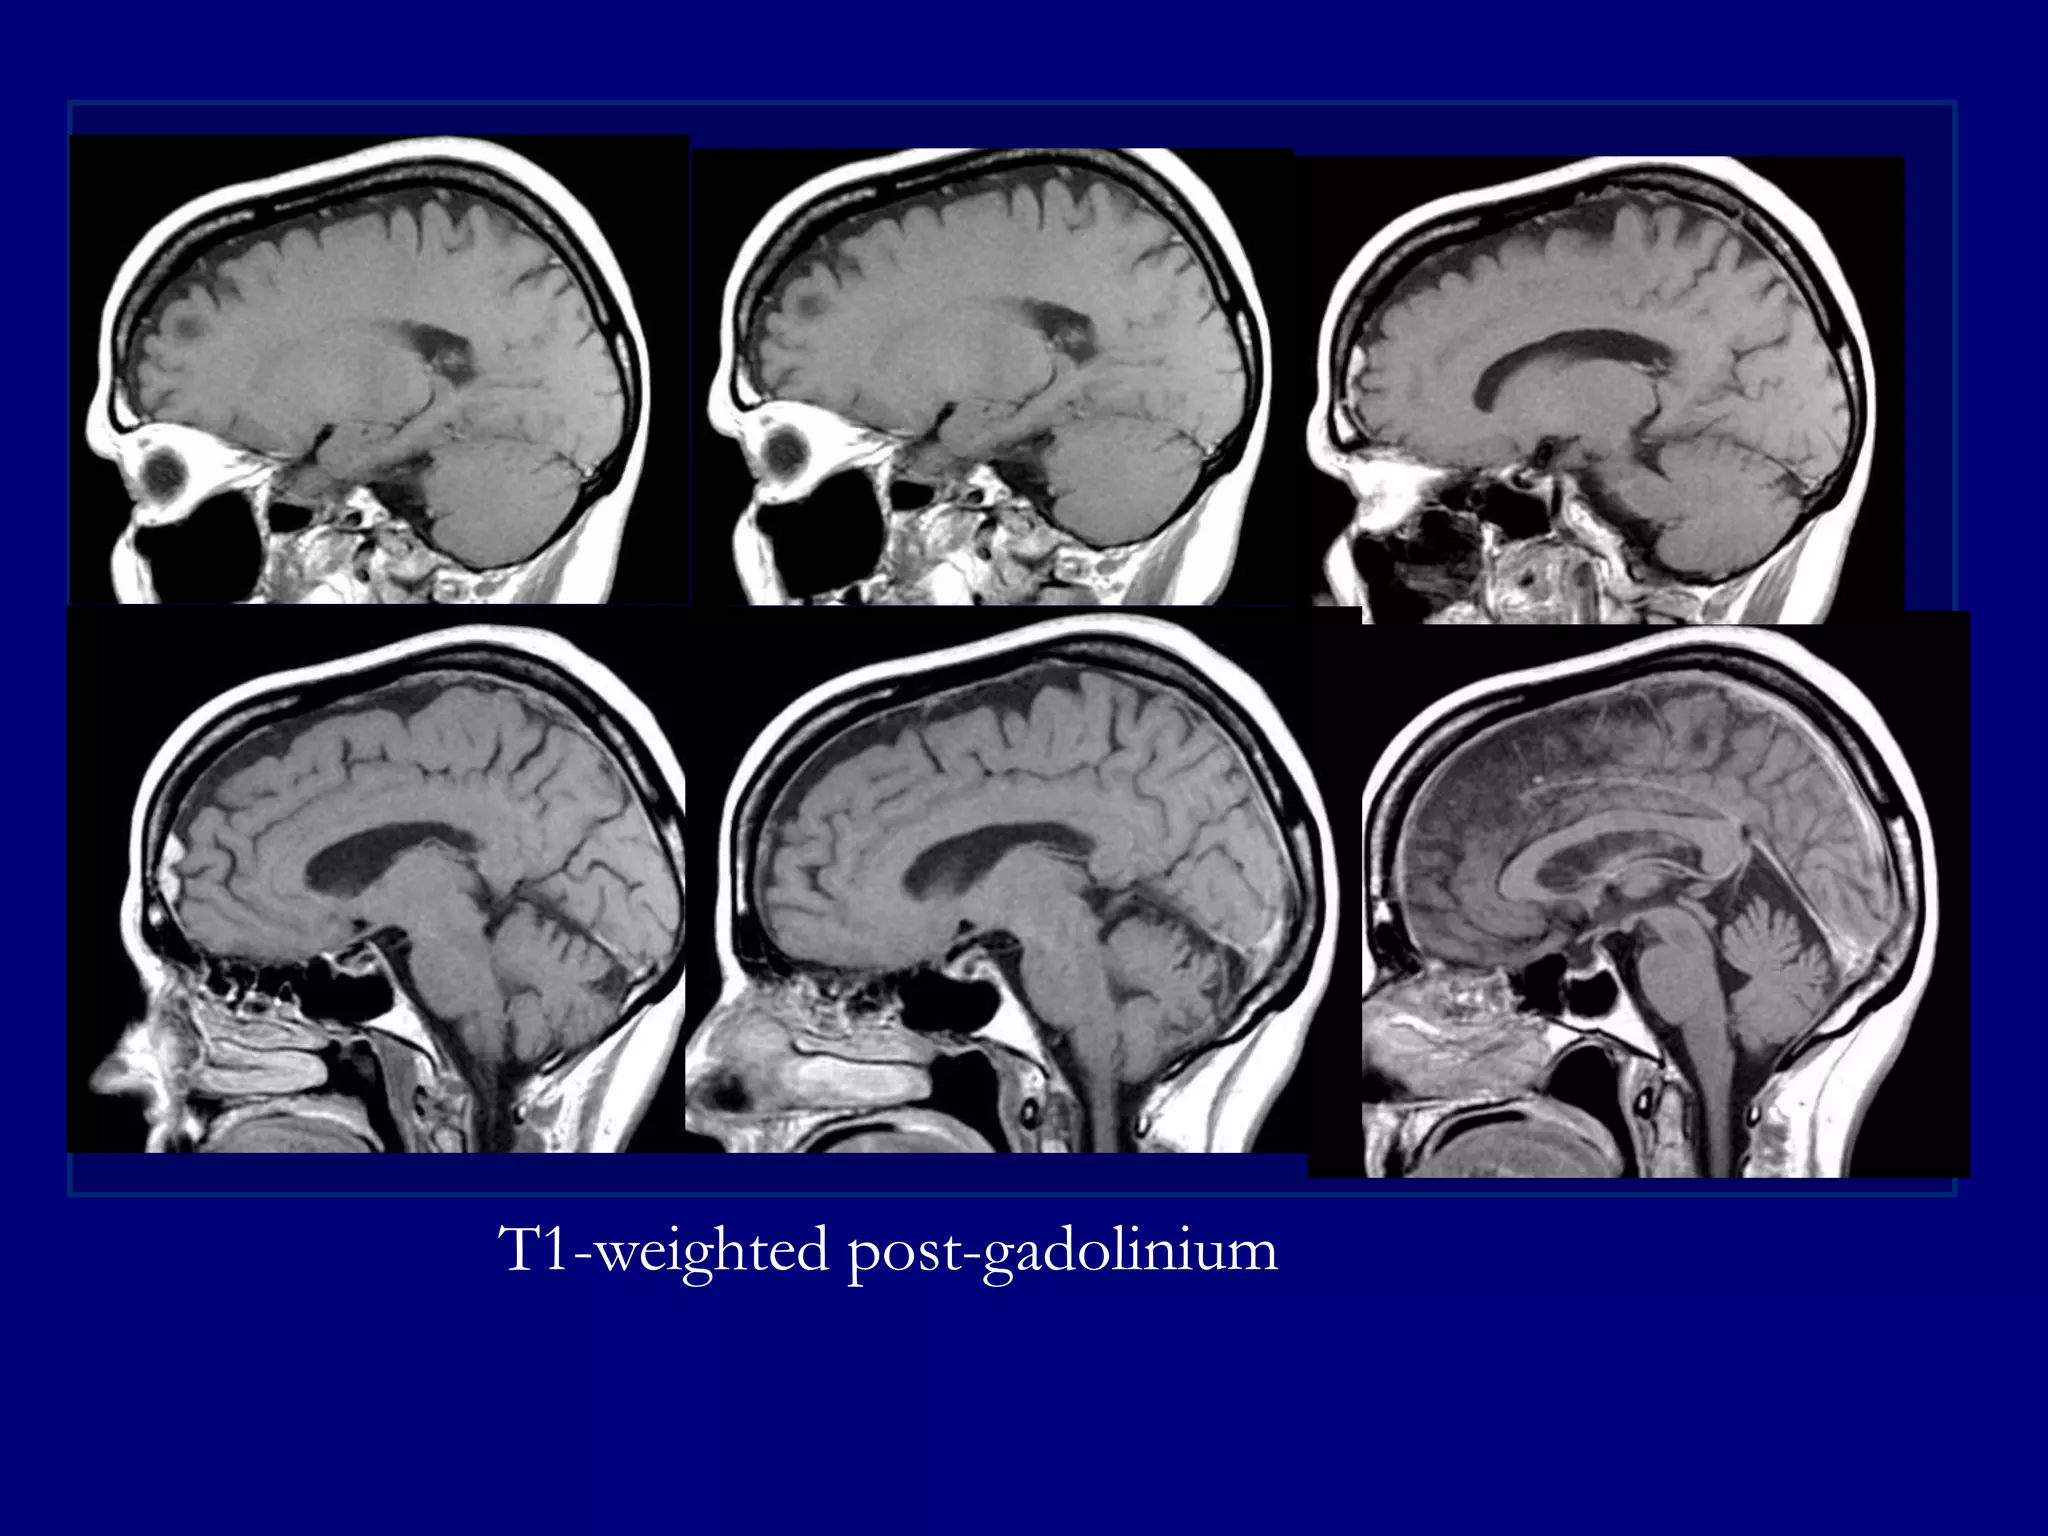

T1-weighted post-gadolinium

MRI 2013

Pre-operative MRI T1-weighted post-gadolinium

Pre and post-gadolinium T1-weighted

Post-gadolinium MPRAGE